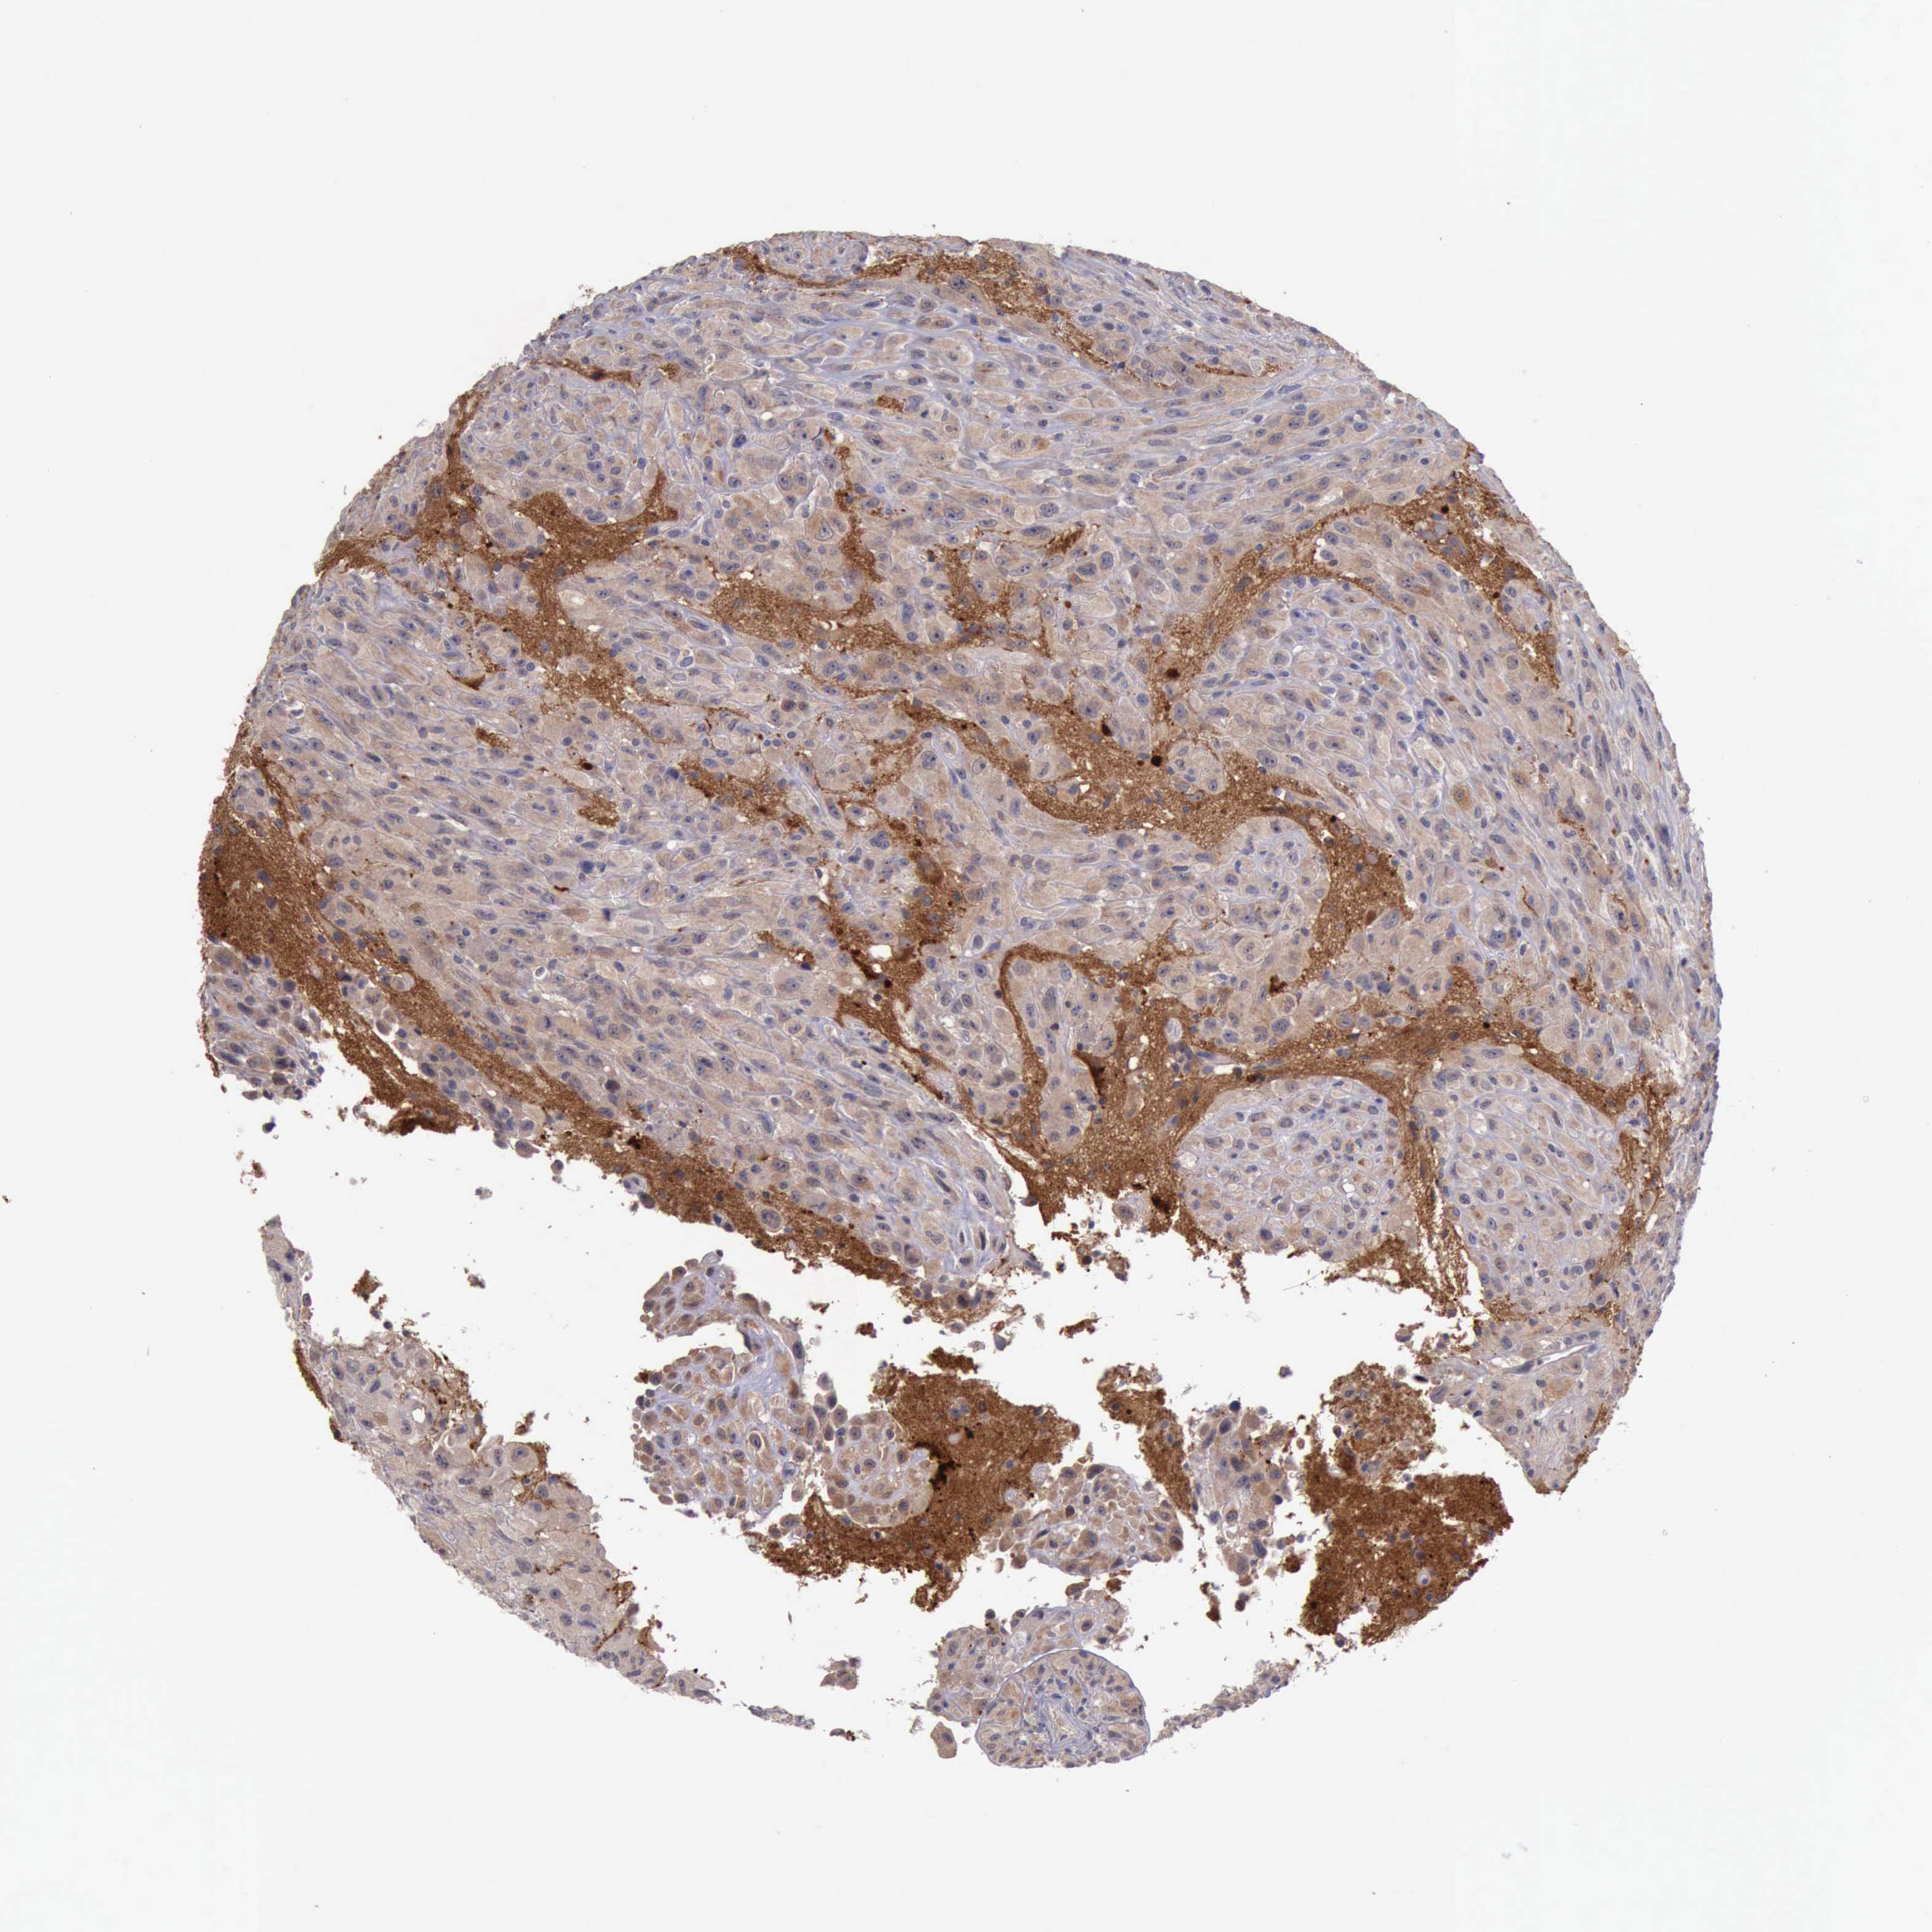

GLIOMA - Protein expressioni

A mouse-over function shows sample information and annotation data. Click on an image to view it in a full screen mode. Samples can be filtered based on level of antibody staining by selecting one or several of the following categories: high, medium, low and not detected. The assay and annotation is described here.

Note that samples used for immunohistochemistry by the Human Protein Atlas do not correspond to samples in the TCGA dataset.

Antibody stainingi

Antibody staining in the annotated cell types in the current human tissue is reported as not detected, low, medium, or high, based on conventional immunohistochemistry profiling in selected tissues. This score is based on the combination of the staining intensity and fraction of stained cells.

Each image is clickable and will lead to virtual microscopy that enables deeper exploration of all samples and also displays staining intensity scores, fraction scores and subcellular localization as well as patient and tissue information for each sample.

Antibody HPA001114

Antibody HPA042505

Staining

High

Medium

Low

Not detected

Intensity

Strong

Moderate

Weak

Negative

Quantity

>75%

75%-25%

<25%

None

Location

Nuclear

Cytoplasmic/membranous

Cytoplasmic/membranous,nuclear

Glioma, malignant, High grade

Glioma, malignant, Low grade